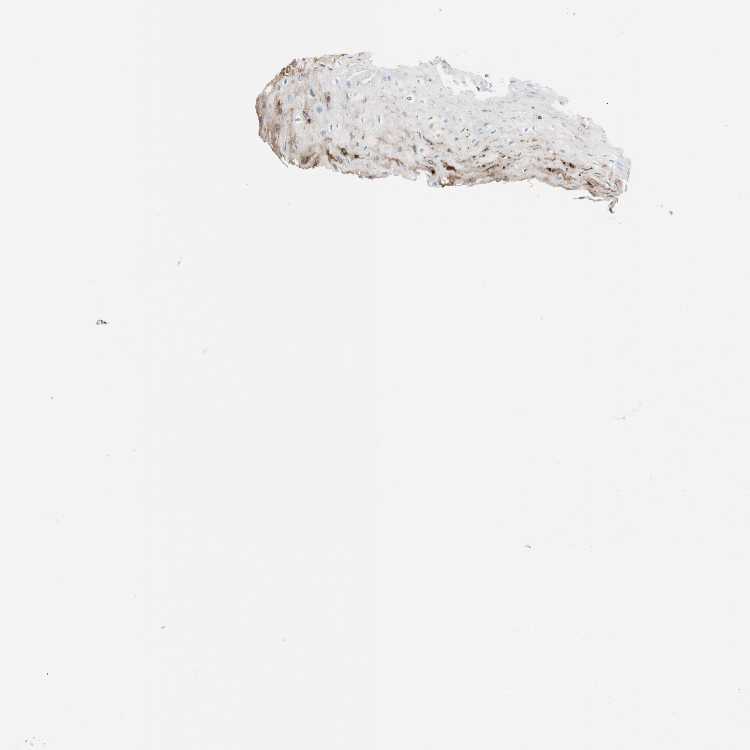

ESOPHAGUS - Antibody stainingi

Antibody staining in the annotated cell types in the current human tissue is reported as not detected, low, medium, or high, based on conventional immunohistochemistry profiling in selected tissues. This score is based on the combination of the staining intensity and fraction of stained cells.

Each image is clickable and will lead to virtual microscopy that enables deeper exploration of all samples and also displays staining intensity scores, fraction scores and subcellular localization as well as patient and tissue information for each sample.

Antibody HPA007316Antibody HPA007571Antibody CAB008636

Squamous epithelial cells Not detectedNot detectedMedium